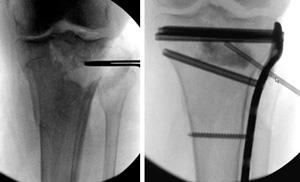

Learn how to prevent and treat them. Tenderness was found over the lateral aspect of the leg, and radiographs showed an area of calcification along the shaft of the proximal fibula. Carrying approximately 17% of your body weight and transferring it from the shin to the foot, supporting your leg, ankle and body muscles. Stress fractures are common injuries in athletes and military recruits. (a) proximal tibial stress fracture (arrow). However, when it happens it usually affects the part just below the knee called proximal tibia. A 45 year old woman with ra the resultant change in clinical outcome/course is outlined in this case report. Fractures may present as pain and tenderness over the lateral proximal fibula or as knee pain. Stress fractures of the fibula are caused by an imbalance between bone formation and bone resorption (removal). Lower end fibula fractures are common in older adults. Biomechanical studies have shown that the fibula receives between 6.4% and 16.7% of the load transmitted from the lower extremity. Rest from training and competition until the local bone tenderness is gone. Fibula fractures are a common injury to the smaller of the two bones that comprise the lower leg. The proximal fibula is the insertion. Learn how to prevent and treat them. Frontal impact at the level of the proximal tibiofibular joint may result in posterior dislocation of the fibular head. • mean age at the time of injury was 7.1.